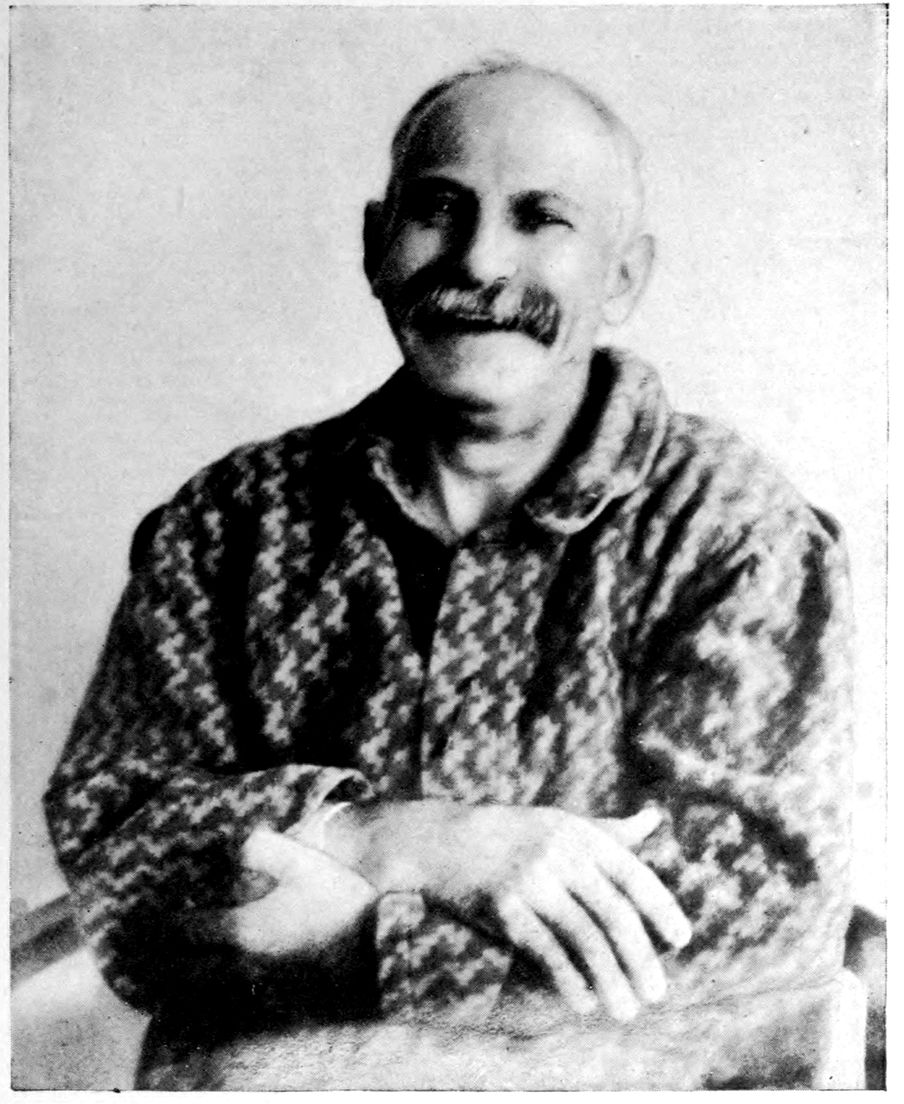

Case 3. James Dixon, 44, was first seen at the Danvers Hospital, reciting verses in a dramatic and noisy way. He remained good-natured and jolly; nor was there any change in his euphoria until he had become physically weaker and more generally demented. In fact, Dixon appeared to become more and more expansive as he became physically weaker. He was in the habit of describing himself as “O. K., No. 1, Superfine.”

Physically the patient was gray and bald on vertex, had a dusky complexion, was very thin (6 ft. in height, weight 155 lbs.); the mucous membranes were pallid; the teeth rather poorly preserved; the heart was somewhat enlarged; the pulse irregular in rhythm, of poor volume and tension.

Neurologically, the patient showed a characteristic Romberg sign and ataxia in walking a straight line. The tremulous tongue was protruded to the left, and there was a coarse tremor of the extended fingers. The knee-jerks were absent, and the Achilles jerks could not be obtained; the plantar reactions were slight; the arm reflexes were present. The pupils were stiff to light. There was a marked vocal tremor. The sensations could not be tested on account of the patient’s mental state.

It appears that Dixon had left school at about 16, at about 22 had gone into the provision business, and later had become a hotel clerk. He had married at 28; there had been two miscarriages, at three months and six weeks respectively; one child was stillborn; four children were living.

The patient was not very alcoholic. The patient’s wife thought the symptoms had been coming on since his forty-first year when irritability set in, but he was not discharged from work until about a year since. He was taken back again after his wife’s pleas, and remained at work about three 38months; but for ten months before admission to the hospital, Dixon had done practically nothing, had shown a marked memory failure and speech defect, at the same time claiming to be a person capable of doing and accomplishing everything. He had become careless of his personal appearance, collected a drawer-full of stumps of cigars, carried lumps of coal in his pocket, laughed causelessly, and spat on the carpet.